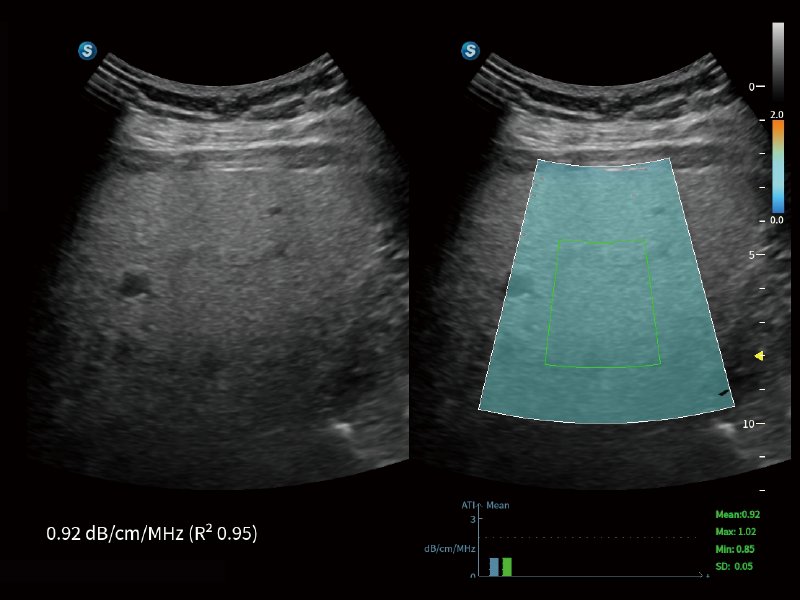

作为开立医疗全新打造的超高端旗舰超声产品,从探头抬起唤醒开启扫查到多维探头发射接收,通过先进的场成像发射、自适应聚合重建等技术,基于RF Data原始射频数据在图像生成、高端功能等方面实现突破,提供多科室综合临床解决方案。

独有场成像发射技术

自适应聚合重建技术

独家XPUs混合硬件架构